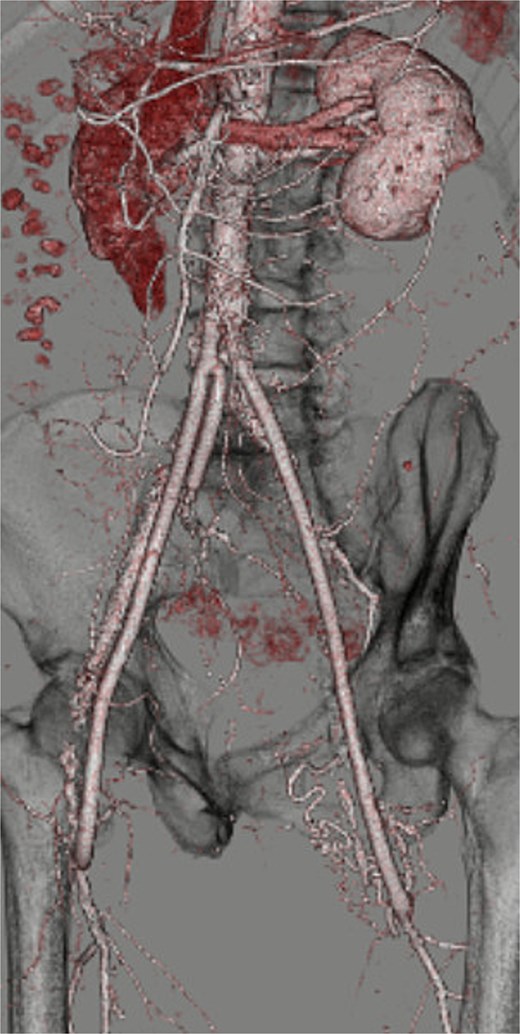

Through a transperitoneal midline incision, the infrarenal abdominal aorta and bilateral iliac arteries were exposed. Bilateral groin incisions were made to isolate the profunda femoris arteries. The peritoneum anterior to both external iliac arteries was incised and extended by blunt dissection to the groins, creating graft tunnels that passed posterior to the ureters. After systemic heparinization, the infrarenal abdominal aorta and right internal and external iliac arteries were clamped without any protection, and the aneurysm sac was opened. Hemorrhage from the lumbar arteries was managed by ligating them from within the aneurysmal sac. The inferior mesenteric artery was occluded with no backflow. A three-branched Intergard graft (17 × 7 × 7 mm; Getinge, Gothenburg, Sweden) was anastomosed end-to-end to the infrarenal aorta. One branch was anastomosed end-to-end to the right internal iliac artery. The remaining branches were passed through the preformed tunnels and anastomosed end-to-side to the bilateral profunda femoris arteries. Because the left profunda femoris artery was calcified and anastomosis was technically challenging, partial endarterectomy was performed. At the other anastomotic sites, neither endarterectomy nor angioplasty was required. The right external iliac artery was oversewn with felt reinforcement, and the left common femoral artery, filled with atheroma and lacking backflow, was not reconstructed because preoperative CT revealed severe calcification of the left superficial femoral artery and the blood flow to the left leg depended mainly on the profunda femoris artery (Supplementary Fig. 1). The operative time was 318 minutes, the aortic cross-clamp time was 23 minutes, and the total blood loss was 208 mL; no blood transfusion was required. Postoperative ABI improved to 0.58 on the right and 0.57 on the left. Postoperatively, the patient received single antiplatelet therapy with aspirin. Postoperative CT demonstrated excellent graft patency, and claudication resolved completely (Fig. 2, Video 2). The postoperative course was uneventful, and no recurrence of claudication was observed during outpatient follow-up. However, the patient experienced sudden unexpected death at home 3.5 years after surgery, with the cause remaining unknown.

Postoperative three-dimensional CT demonstrating well-reconstructed aorto-profunda and internal iliac bypasses.